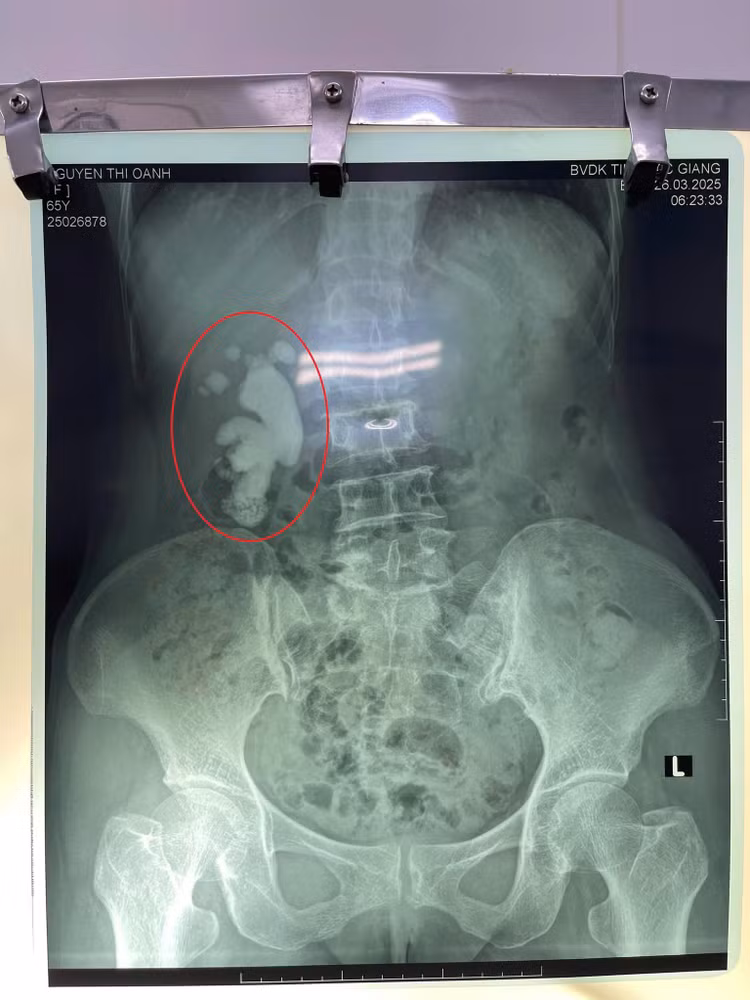

| Kết quả chụp CT cho thấy hình ảnh sỏi san hô thận phải. Ảnh BVCC |